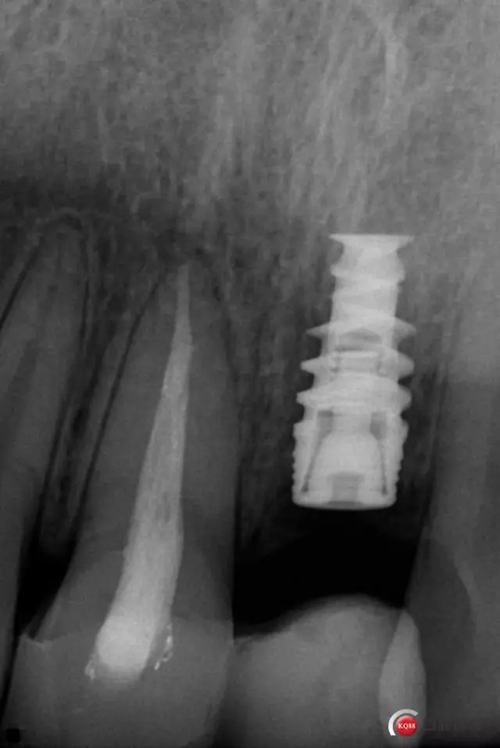

種植后修復(fù),我們要把握每一個細(xì)節(jié),比色,轉(zhuǎn)移桿的就位,我們必須把臨床做好,技工師傅才會給我們做出好的修復(fù)體,減少一些不必要的失誤,首先術(shù)前的檢查是必要一步 ,再是器械的準(zhǔn)備使我們臨床操作有條不紊,術(shù)前拍照,o-bite取咬合記錄,消毒修復(fù)術(shù)區(qū),旋出愈合基臺,生理鹽水沖洗袖口,拍照袖口,安放合適轉(zhuǎn)移桿,拍X線見轉(zhuǎn)移桿就為良好,硅橡膠取模,術(shù)后旋回愈合基臺,拍照比色。